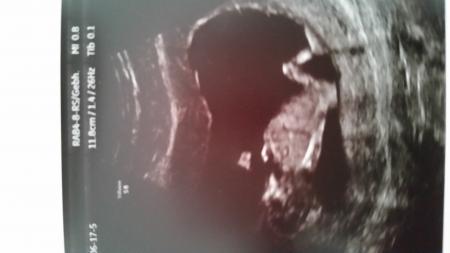

Habe Euch jetzt seit ca. 3 Wochen heimlich beobachtet . Ich hatte gestern auch das Erst Trimester Screening und den wollte ich abwarten. Nach ersten Einschätzungen vom FA ist aber alles gesund und da wo es hin gehört. Naja, nur dass unser Wurm schon sehr groß ist (5,9 cm). Mein FA hatte erst 11+2 (17.06.) berechnet. Gestern meinte er, dass es auch schon 12+2 sein könnte.

Herzlich willkommen. und dir auch eine schöne kugelzeit. Dein foto vom wurm ist echt super schön. Lg schubbel

Ja, der FA hat sich echt Zeit gelassen mit dem Ultraschall. Hat sogar die Finger nachgezählt. Der Papa war auch mit dabei und hat so viel gefragt. War richtig süß (psst... das wollen Männer nicht hören). Könnten sogar erkennen, wie unser Baby sich gestreckt hat.. Es ist echt der Wahnsinn, wie sich alles so entwickelt.

Wowwww, das sieht ja schon echt nach Baby aus, was so 2 Wochen doch ausmachen können. Ich war Montag bei 8+1 zum US, das sah noch nach Wurm aus